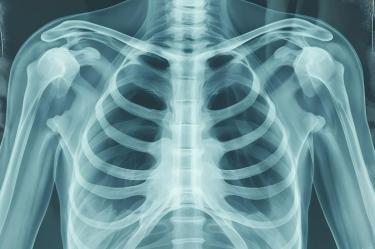

Los peligros de una infección respiratoria no tratada incluyen neumonía, sepsis y, en casos extremos, meningitis o edema cerebral. Estas complicaciones ocurren cuando el sistema inmunológico es superado, permitiendo que la inflamación afecte tejidos distantes.

El edema cerebral es la acumulación de líquido en el cerebro que genera presión intracraneal. Si una infección respiratoria se vuelve invasiva, puede bloquear el flujo sanguíneo, provocando una falta de oxígeno u isquemia cerebral con consecuencias fatales o permanentes.

La sepsis es una emergencia médica donde el cuerpo se ataca a sí mismo al intentar combatir la infección. Si los pulmones o la tráquea están comprometidos, las bacterias pueden entrar al flujo sanguíneo y causar fallas orgánicas múltiples en cuestión de horas.

Expertos de la Cleveland Clinic señalan que el manejo temprano de los síntomas evita la formación de abscesos periamigdalinos. Estos abscesos pueden obstruir las vías aéreas o propagar la infección hacia los tejidos profundos del cuello y el tórax.

- Dolor en el pecho: Puede indicar que la infección ha llegado a la pleura o al tejido pulmonar.